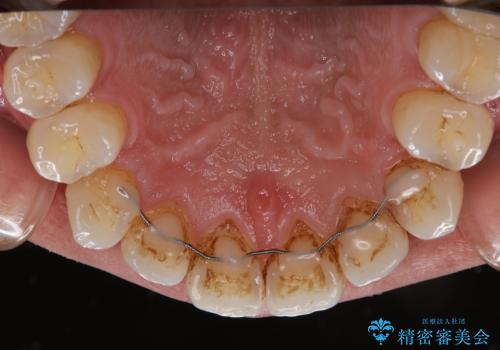

また、以前他院にて矯正治療を行い、前歯の裏側には保定装置がついていることで磨きにくいため機械的に細かい部分のクリーニングも希望とのことでした。

エアフローワンは、特殊なパウダーを混ぜた水を水面にジェット噴射することでバイオフィルム(プラーク)・ステイン(着色)・早期歯石を天然歯やインプラント周囲から除去することが可能な歯面清掃器具です。

従来の荒い研磨剤などを用いた歯面への負担が大きいクリーニングとは異なり、歯質の負担を最小限にした歯面清掃と歯周ポケット内のメンテナンスを行えます。